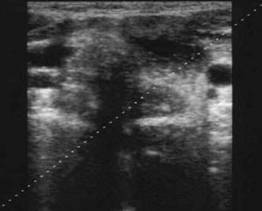

Femeie

de 23 ani. Chist mare (25x29x43mm, 16 cc) in lobul stang, marcant hipoecogen,

cu septe in interi si intarire posteriore.

Examen citologic: pseudochist coloid.

Aceeasi pacienta. Vascularizatie numai in periferie.